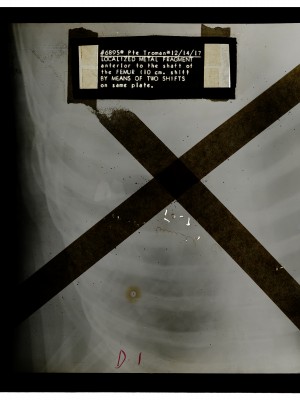

Dr. Edwin Ernst, an only child born to St. Louis residents Charles and Catherine Ernst, was a notable Roentgenologist, a physician who specializes in radiological work. Dr. Ernst studied at Washington University in St. Louis and later at Moravian College in Bethlehem, Pennsylvania earning his advanced degrees. For two years he served as a resident physician at the St. Louis Mullanphy Hospital before leaving to pursue a private practice. When the United States formally entered the war in 1917, Ernst left St. Louis to become chief radiologist at Base Hospital 21. He was discharged honorably in 1919 with the citation of Major. His collection consist of x-ray images taken at Base Hospital 21 as well as drawings of radiological equipment and photographs.